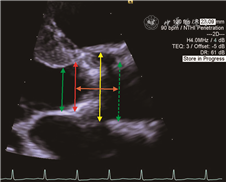

1.经导管二尖瓣缘对缘修复术中超声的应用:术中采用超声引导主要包括以下几个步骤:(1)引导房间隔穿刺:穿刺部位一般选择在房间隔后上方,四腔心切面测量穿刺点距二尖瓣瓣环距离在4~4.5 cm处较为理想(图4)。(2)引导输送装置进入左心房:此过程中需不断微调探头角度始终清晰显示输送装置头端,避免损伤心房壁。结合应用3D TEE可实时显示输送装置头端在左心房内的空间位置关系。(3)引导夹合器到达二尖瓣病变位置上方并调整夹合器的方向使夹合器双臂连线与瓣叶闭合线垂直(图5)。(4)引导二尖瓣叶抓捕(图6)。(5)抓捕瓣叶后评估夹合器稳定性、残余反流程度、测量二尖瓣口,若结果满意则可完全释放,若残余反流较多且无明显狭窄,可放入第2枚甚至第3枚夹合器。(6)引导器械完全撤回后,再次评估夹合器稳定性、MR程度、二尖瓣口PGmean以及房水平分流情况,3D TEE可清晰显示二尖瓣双孔化(图7)。

LA为左心房,RA为右心房,SVC为上腔静脉,LV为左心室,RV为右心室

LA为左心房,LV为左心室

LA为左心房,LV为左心室,A2为二尖瓣前瓣A2区,P2为二尖瓣后瓣P2区

AO为主动脉